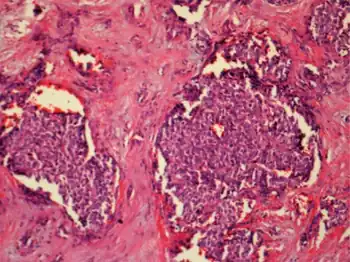

| File:11154 2020 9548 Fig1 HTML.webp | |

| Diagrammatic representation of β-cell function, genetic defects are included in red.[1] | |